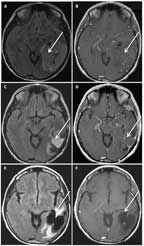

FIGURE 3

MRI of a 54-Year-Old Woman With an Anaplastic Oligodendroglioma, IDH1- Mutant, 1p/19q Codeleted

A 54-year-old woman presented with several years of progressive cognitive impairment. An MRI revealed a large, 7.7 × 5.6-cm calcified, nonenhancing lesion within the left temporal and parietal lobes (Figures 3A and 3B). Using preoperative speech mapping and awake surgery, a gross total resection of the tumor was achieved (Figures 3C and 3D). Pathology was anaplastic oligodendroglioma. Retrospectively, the patient’s tumor was found to have IDH1 R132H mutation and 1p/19q codeletion. Postoperatively, she received 18 cycles of temozolomide alone. She remained progression-free for over 6 years, when imaging revealed a slowly expanding, nonenhancing asymptomatic lesion. She underwent a second gross total resection, and the pathology remained anaplastic oligodendroglioma. Postoperatively, she was treated with radiation (60 Gy). Currently, 8 years after her diagnosis, she remains radiographically stable (Figures 3E and 3F) and neurologically intact.